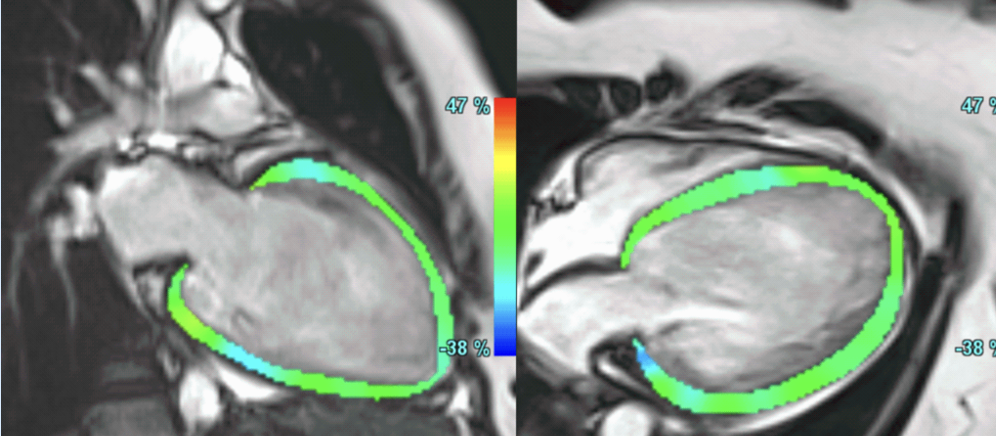

A common clinical presentation of LBBB induced cardiomyopathy is described in this post. It is always dilemma that if LBBB is cause or effect of dilated cardiomyopathy. However CMR can help in differentiating it from other causes and also in predicting response to device therapy. Utilise CMR to the fullest..!